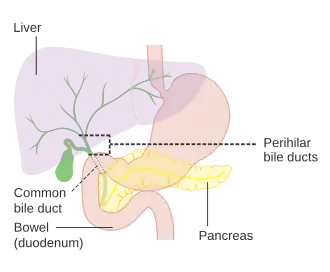

Diagram of the biliary tree showing the common bile duct | |

The common bile duct (also bile duct) is a part of the biliary tract.[1][4] It is formed by the union of the common hepatic duct and cystic duct. It ends by uniting with the pancreatic duct to form the ampulla of Vater (hepatopancreatic ampulla). Its sphincter the sphincter of Oddi, enables the regulation of bile flow.

The bile duct is some 6–8 cm long, and normally up to 8 mm in diameter.[4]

Its proximal supraduodenal part is situated within the free edge of the lesser omentum. Its middle retroduodenal part is oriented inferiorly and right-ward, and is situated posterior to the first part of the duodenum, and anterior to the inferior vena cava. Its distal paraduodenal part is oriented still more right-ward, is accommodated by a groove upon (sometimes a channel within) the posterior aspect of the head of the pancreas, and is situated anterior to the right renal vein.[4]

The bile duct terminates by uniting with the pancreatic duct (at an angle of about 60°) to form the Ampulla of Vater (hepatopancreatic ampulla).[4]

Several problems can arise within the common bile duct, usually related to its obstruction. Opinions vary slightly on the maximum calibre of a normal CBD, but 6 mm is one accepted upper limit of normal [5] with a further 1mm diameter allowed for each decade over 60 years.

On abdominal ultrasonography, the common bile duct is most readily seen in the porta hepatis (where the CBD lies anterior to the portal vein and hepatic artery). The absence of Doppler signal distinguishes it from the portal vein and hepatic artery.

Borderline of a dilated perihilar bile duct, measuring 8 mm.

Borderline of a dilated perihilar bile duct, measuring 8 mm. -